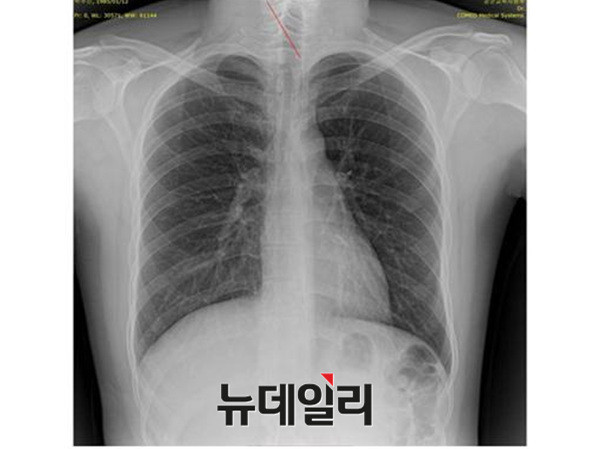

미래창조과학부 산하 동남권원자력의학원 암센터 병원장까지 지낸 영상의학전문의의 눈에 들어온, 박주신씨 명의의 MRI 속 인물의 나이는 적어도 35세 이상이었다.

양승오 박사는, 주신씨 명의의 허리 MRI 사진을 통해 확인할 수 있는 ‘골수신호강도’를 주장의 근거로 제시했다.

양승오 박사가 근거로 든 ‘골수신호강도’는 국제축구연맹(FIFA)이 청소년축구대회 참가 선수들의 연령대 판별을 위한 지표로 쓸 만큼, 정확도가 높다.

양승오 박사는 주신씨 명의 허리 MRI 사진에 대한 판독결과, “MRI 속 피사체가 20대 청년일 확률은 0%에 가깝다”고 밝혔다.

그런 그의 눈에 들어온 세브란스병원 MRI 영상자료는 아무리 봐도 20대 청년의 것이 아니었다.

국제축구연맹이 청소년 축구대회에 출전한 선수들의 나이를 감별할 때도 쓴다는 ‘골수신호강도’를 기준으로 볼 때, 박주신씨의 신체를 촬영했다고 하는 세브란스병원 MRI 영상자료 속 피사체의 연령대는 적어도 35세 이상이었다.

양 박사가 근거로 삼은 ‘골수신호강도’는 일반인에게는 매우 낯선 용어다. 용어만이 아니라 MRI 영상자료를 보면서, 해당 피사체의 골수신호강도를 근거로 연령대를 판별하는 것은 매우 전문적인 영역의 사안이다.

“연세대 MRI, 이래서 믿기 어렵다”

“골수신호강도를 통해 본

연세대 MRI 촬영 남성은 최소 35세”연세대 MRI 자료와 관련돼 양승오 박사가 제기한 의혹의 근거에는 [골수신호강도]라는 것이 있다. MRI로 촬영한 영상을 통해 드러나는 환자의 골수상태를 식별하는 표지라고 할 수 있는데, 특히 사람의 신체 나이와 밀접하게 관련돼 있다.

국제축구연맹(FIFA)은 20세 이하 청소년 경기를 하기 전, 선수들의 손을 찍은 MRI를 통해 나이를 감별하고 있다.

MRI 촬영을 통해 드러난 선수들의 성장판 양상과 [골수신호강도]를 근거로, 출전 선수들의 신체 연령대를 확인하는 것.

이렇듯 사람의 신체 나이를 판별하는 바로미터인 [골수신호강도]를 기준으로 할 때, 연세대 MRI 사진 속 남성은 ‘어릴 적 아주 불우한 삶을 살았거나 30대 후반 이상’이라는 것이 양승오 박사의 의학적 소견이다.

다음은 연세대 MRI 사진 속 남성의 [골수신호강도]와 관련된 양승오 박사의 설명으로, 2013년 5월21일 있었던 <뉴데일리>와의 단독인터뷰 중 일부를 요약 정리한 것이다.

기자 : 박주신씨 ‘MRI 골수 신호강도’에 어떤 문제점이 있다는 것인가.

양승오 박사 : “언론을 통해 알려진 T2영상 신호강도에 따르면, 적색 조혈 골수와 황색 지방 골수가 불규칙하게 섞여 있는데, 이는 20대의 골수에서는 상당히 찾아보기 힘든 패턴이다.

골수는 적색의 조혈 골수와 황색의 지방 골수로 이뤄지는데, 나이가 들면서 황색의 지방 골수가 늘어나게 된다.

10~20 세 남성은 24.6%의 황색 지방 골수(yellow fatty marrow) 분포를 보이지만, 21~30세 남성은 33.5%, 31~40세 남성은 41.4%, 41~50세 남성은 47.6%의 황색 지방 골수 분포를 보인다.

이러한 연령대별 골수강도를 고려할 때, 박주신씨의 MRI 영상에 나타나는 골수강도는 최소 35세 이상에 가까운 상태다.

20대로서는 불가능한 골수강도라 할 수 있다. 만약 박주신씨가 정말 심한 ‘골초’라면, 골수의 변화가 가능하다. 그러나 박주신씨는 비흡연자로 알려져 있지 않은가.

이에 해당 MRI 영상은 박주신씨의 것이 아닐 가능성이 의학적으로 아주 높다.

참고로 연세대 발표 사진과 35세 남자의 척추영상 MRI 증례를 비교해 보면, 연세대 사진에서 흰색으로 나타나는 지방골수가 불규칙한 양상을 띠면서 증가돼 있다는 사실을 알 수 있다”

연세대 MRI 미스터리, 해외 전문의들의 의학적 소견“해당 요추 MRI는 36~40세 남성의 것”

연세대 세브란스 병원이 촬영한 박주신씨 허리 MRI 사진에 대한 의문은 해외 의학자 사이에서도 나오고 있다.[영상의학계의 석학]이라 불리는 ‘주세페 굴리엘미’ 박사는 박주신씨 MRI 사진 자료를 접한 뒤 다음과 같은 반응을 보였다.

“In regard to your question due to the BM aspect and the disc signal,

I believe that this lumbar MRI can be attributed to a male of 36-40 years old.골수양태와 추간판 신호에 근거해 답을 드리면, 해당 요추 MRI는 36~40세 남성의 것으로 볼 수 있다”

‘주세페 굴리엘미’(Giuseppe Guglielmi) 박사는, 유럽 근골격 방사선학회 골다공위원장으로, 이탈리아 Foggia 대학교 영상의학과(방사선학) 교수다.아시아근골격학회(AMS) 회원이자 태국 Chiang Mai 대학교 교수인 너트(Nutaya) 박사 역시, 비슷한 소견을 밝혔다.

“late 40 to 60 I guess.

Bone marrow of adult, disc bulge a little bit, mild flavum thickening, and considerable amount of visceral fat. Surprising that the retrolisthesis didn't cause pain.

40대 후반에서 60대로 추측된다.

성인의 골수, 디스크 약간 돌출. 인대가 두꺼워져 있고 상당한 양의 내장지방이 보인다. 척추전위증이 통증을 수반하지 않았다는 것이 놀랍다”

MRI 촬영 당시 박주신씨의 나이는 27세. 그러나 MRI 영상의 주인은 약 40~60대로 추정된다는 것이 해당분야 전문가들의 공통 소견이다.전문가들의 견해를 종합하면, 박주신씨는 일반인보다 최소 10~20년 이상을 앞서 살고 있다는 결과가 나온다.